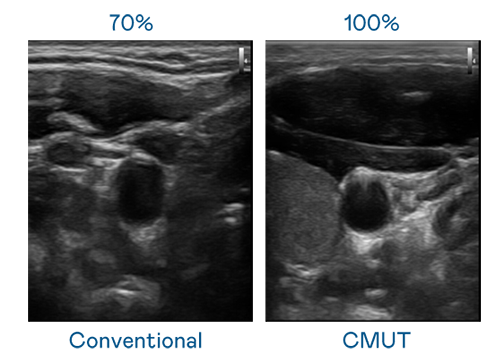

CMUT 技术是一种用电容式微机电元件来产生超音波讯号的技术。与传统 PZT 压电式技术相比,CMUT 频宽增加 30%,更宽频的超音波讯号让影像解析度大幅提升,是实现高影像品质医疗超音波扫描、促进精准医疗发展的关键技术。

超音波影像的解析度高低,首先取决于探头能发出的讯号频宽。哈希游戏 CMUT 可提供高清晰的超音波讯号,提供高频宽、高灵敏度、影像纹理细节更高的超音波影像,协助医护人员缩短影像判读时间及利用精准的医疗影像进行诊断。